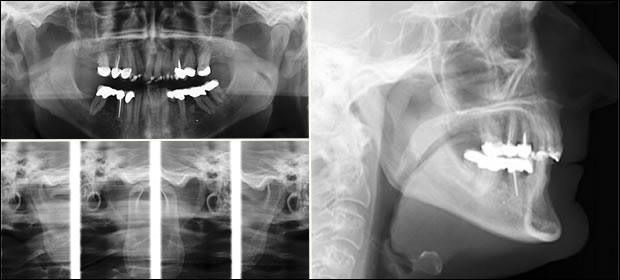

Fig 6: Diagnostic images for this case included a panoramic image, trancranial images of the temporo-mandibular joints in the closed and open positions, as well as a cephlometric image.